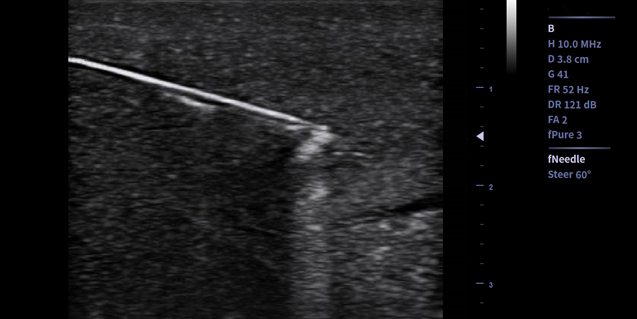

适用于浅表组织、小器官,神经,血管等